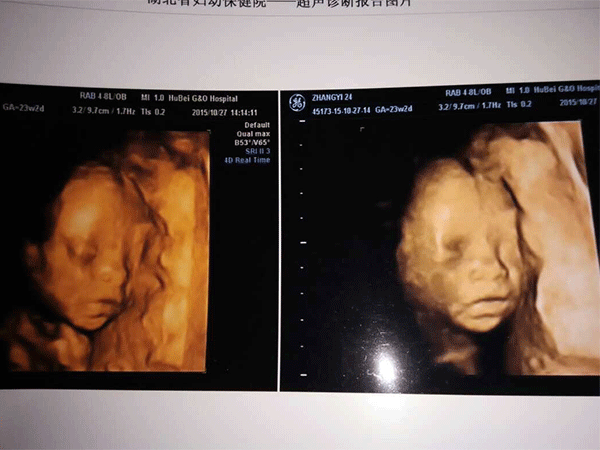

三维彩超,即彩色多普勒超声检查的一种,检查图像呈土黄色,通过多普勒超声仪器发出超声波,对体内各项器官进行成像。三维即其图像是立体的,可以更直观的看到器官的形态,及时发现病变并进行治疗。三维彩超常用于产检,用来判断胎儿的生长发育的情况或是否出现畸形等。

产检中,三维彩超通过测量子宫纵径、子宫体横径、子宫前后径这三条径线来观察胎儿是否正常。以及通过三维立体的成像,可以清晰的显示出胎儿各个内脏器官,以及面部器官、四肢的情况,来简单的判断胎儿是否存在畸形,包括胎儿是否患有先天性心脏病也是能够检查出来的。

答案:三维彩超的检查时间是在22周-26周左右,其中,24周,也就是5-6个月去检查是最理想的。

24周的胎儿,其身体结构的生长发育已经很完善了,且胎儿大小也很合适,这时候做三维彩超可以很直观的看到胎儿的五官四肢、以及内脏器官,还能了解胎儿双顶径、头围、腹围、股骨长等发育情况。

怀孕三维彩超检查报告解读

其实,不会看三维彩超报告单也没有关系,毕竟孕妈不是专业的医生。但如果孕妈想试着了解一下该怎么看的话,可以从胎儿的头围、胎心、胎盘、股骨距离、脐带、羊水等方面入手。这也是B超医生在看数据时最喜欢看,也是最重要的几项。